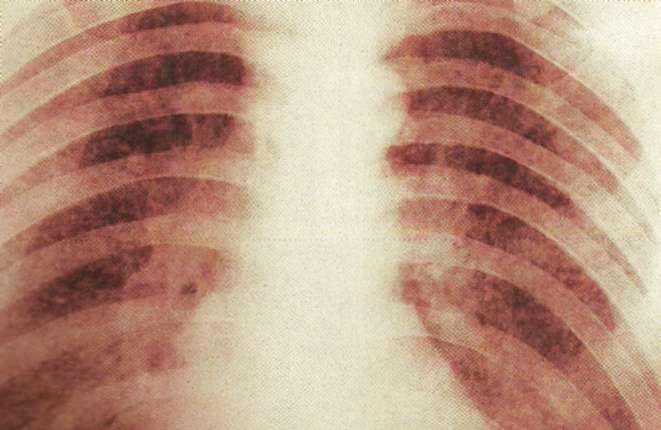

Radiografiile toracice ajută la stabilirea diagnosticului de tuberculoză. în acest caz, prezenţa a mii de noduli foarte mici la nivelul plămânilor indică prezenţa tuberculozei miliare.

Radiografiile toracice pot ajuta la punerea diagnosticului, arătând aspecte caracteristice, cum ar fi umbre şi calcificări în lobii superiori ai plămânilor.